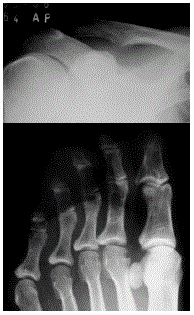

Paciente de 45 anos, feminina, com fraqueza muscular, perda de apetite, fadiga, formigamentos, constipação e dor abdominal. Relata estar em uma fase difícil da vida e muito estressada, o que está promovendo dificuldade de concentração e confusão mental.

Baseado na imagem disponibilizada, qual o seu diagnóstico?